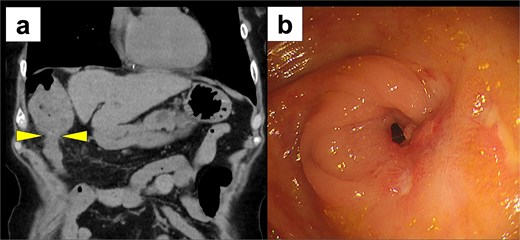

Two months later, the patient was readmitted with disorientation. On arrival, her Japan Coma Scale score was 3. Laboratory findings showed normal liver function (AST 17 U/l, ALT 9 U/l, total bilirubin 1.2 mg/dl) but a markedly elevated ammonia level of 245 μg/dl. CT imaging revealed transverse colon stenosis and massive fecal impaction in the ascending colon (Fig. 3a). Lower gastrointestinal endoscopy showed severe stenosis at the hepatic flexure of the transverse colon, leading to obstruction (Fig. 3b). The stenosis was attributed to ischemic scarring from the previous hernia. A diagnosis of secondary hepatic encephalopathy to constipation due to transverse colonic stenosis was made. Two sessions of endoscopic balloon dilation were performed, resulting in improved colonic patency. We treated the patient with two endoscopic balloon dilations. The first session involved a controlled radial expansion balloon (Boston Scientific) with a diameter of 12 mm. The balloon was inflated to 10 psi for 1 min twice. The second session was performed after 2 weeks and involved the same balloon type, which was inflated to 15 mm. At 8 months follow-up, the patient remains asymptomatic, with no recurrence of DH or hepatic encephalopathy, and continues regular outpatient follow-up.

Postoperative imaging studies. (a) CT scan showing stenosis of the transverse colon with massive fecal impaction in the ascending colon (arrow) and massive fecal impaction in the ascending colon. (b) Lower gastrointestinal endoscopy revealing severe stenosis at the hepatic flexure of the transverse colon.